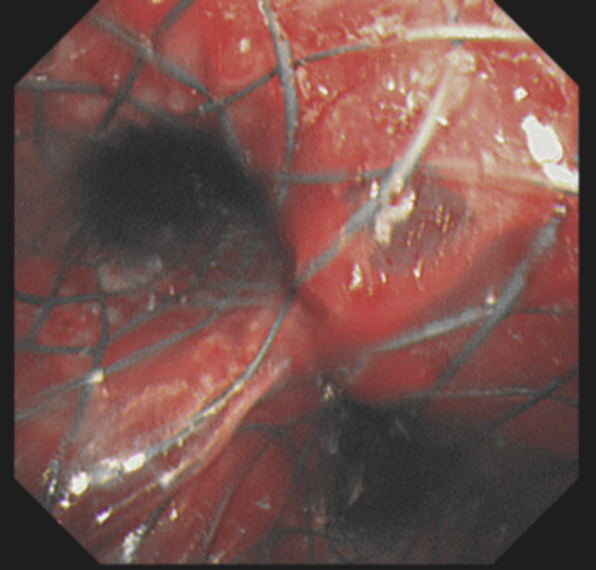

76 岁的刘师傅(化姓),去年在武汉市肺科医院确诊为晚期肺癌合并肺结核感染。上月底,老人病情加重,紧急前往武汉市肺科医院住院进行抗肿瘤、抗结核治疗。本月初,刘师傅突然出现呼吸困难、咯血、高烧等症状,检查发现,右肺肿瘤已经突破原有病灶,长进右主支气管,又通过右主支气管进一步蔓延到左主支气管及主气管下段,肺部感染也明显加重。CT 下可见,大块的肿瘤卡在了主气管与左右主支气管分叉的隆突处。右肺的呼吸通道被完全堵住,左肺仅有一丝狭窄缝隙可以进出空气。

救治过程中,麻醉科团队密切监控患者生命体征及相关状态,及时应对。在内镜中心主任靖秋生统一指挥下,副主任医师胡智敏、主治医师吴鸣镝等人快速插入硬质气管镜,争分夺秒实施支架植入术。助手则准备好封堵球囊、导丝等多种器械,随时应对术中可能发生大出血等并发症。5 分钟后,Y 型支架被成功植入患者气道,位置良好,患者气管、双侧主支气管瞬间恢复通畅,并且没有发生大出血等严重并发症。

内镜中心主任靖秋生表示,Y 型覆膜支架植入后,相当于给「塌方」的气管、支气管,撑起了一条钢结构的畅通「隧道」,「隧道」可以排除肿瘤影响,让这段呼吸通道保持畅通,这将为肿瘤治疗赢得时间。